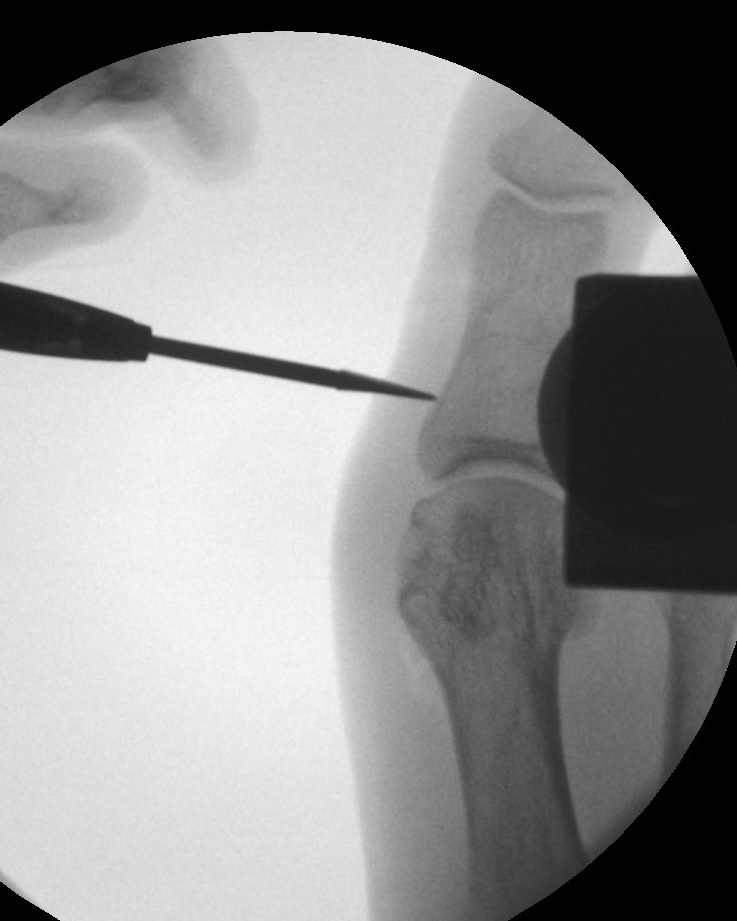

• Fräse mit hohem Drehmoment (3000-6000 U/min) mit Fräskopf (konisch).

• Spülsystem zur Kühlung, alternativ kontinuierliche Kühlung über eine Spülkanüle.

• Bildverstärker.

Operationstechnik (Text und Fotos)